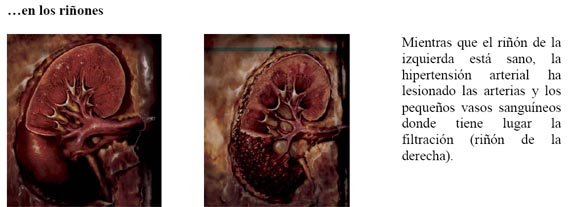

Una persona con hipertensión arterial tiene la pared de la arteria endurecida y engrosada, lo que es menos capaz de dilatarse y comprirse. Como consecuencia, necesita una fuerza mayor para bombardear la sangre a través de la arteria. Esto es responsable de unas siete millones de muertes al año y causa lesiones en el corazón, los ojos, el cerebro y los riñones.